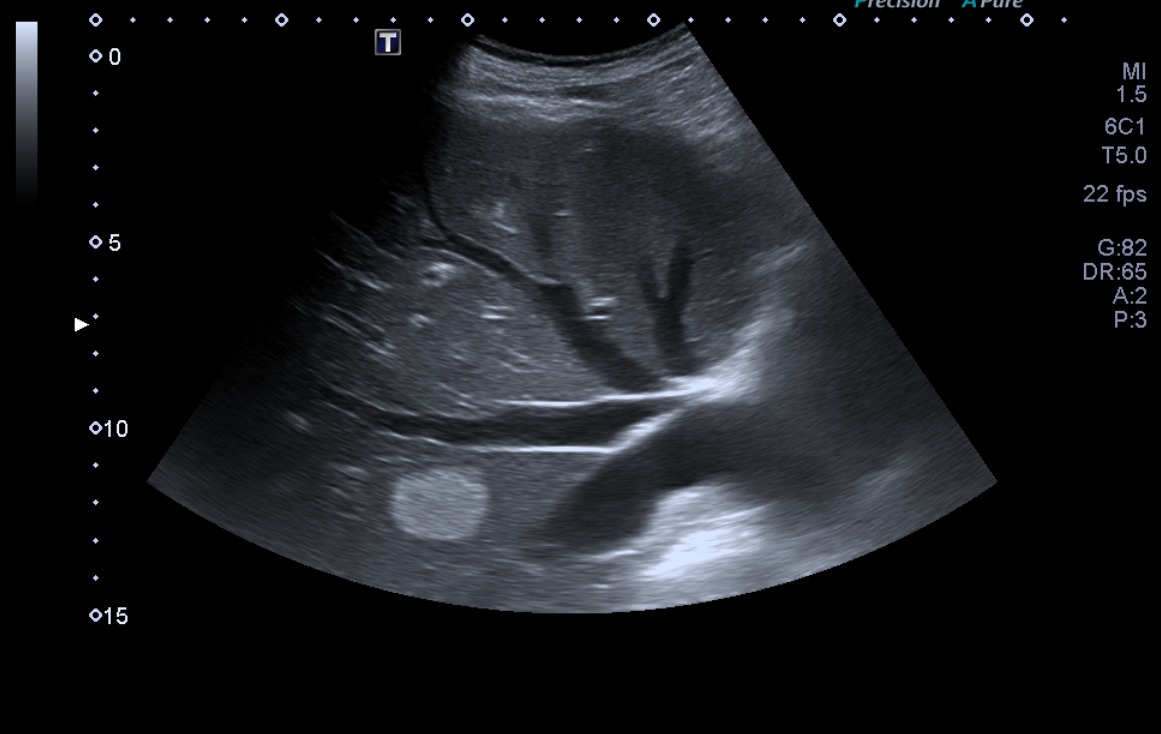

• Ecografía 2 (actual): lesión hiperecogénica en lóbulo hepático izquierdo, no visualizada en el estudio previo. Pared de vesícula biliar engrosada globalmente, 5 mm.

En el contexto de la sintomatología del paciente, los antecedentes, y las características de la imagen hepática de nueva aparición en ecografía, se plantea el diagnóstico de una probable metástasis hepática.